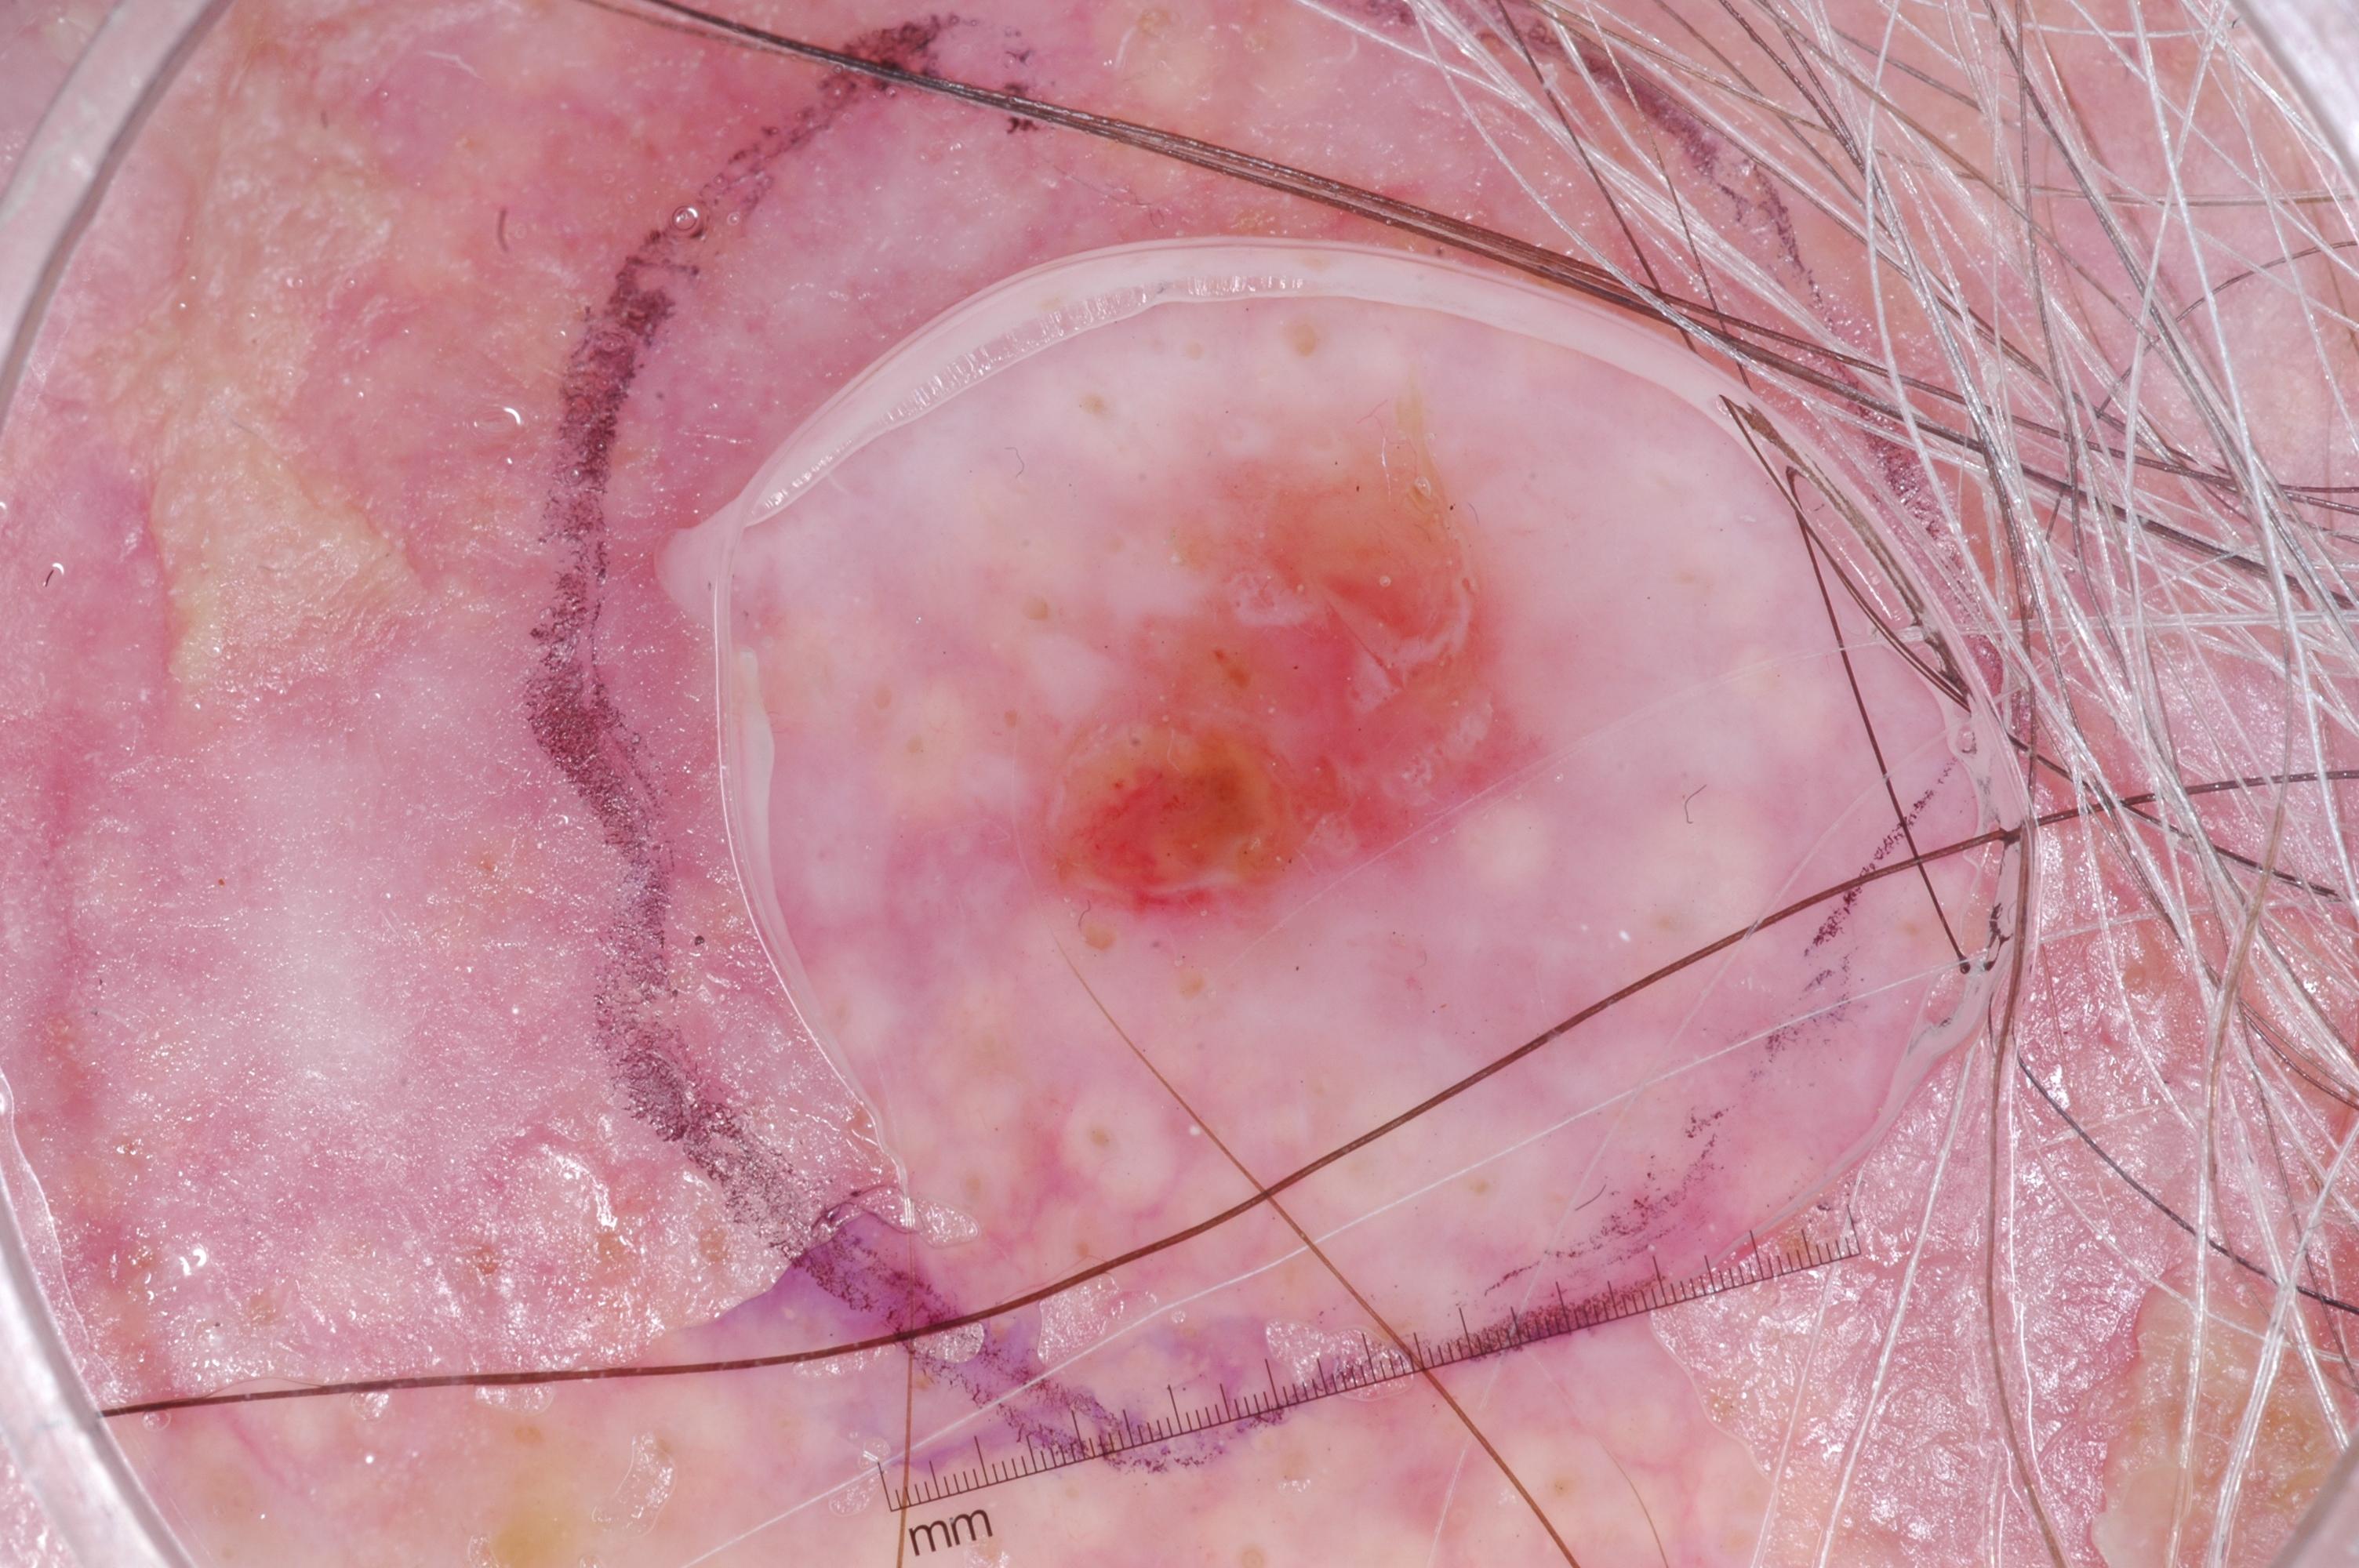

{

"age_approx": 65,

"anatom_site_general": "upper extremity",

"concomitant_biopsy": true,

"dermoscopic_type": "contact non-polarized",

"diagnosis_1": "Malignant",

"diagnosis_2": "Malignant melanocytic proliferations (Melanoma)",

"diagnosis_3": "Melanoma Invasive",

"diagnosis_4": "Melanoma Invasive, Associated with a nevus",

"diagnosis_confirm_type": "histopathology",

"image_type": "dermoscopic",

"lesion_id": "IL_6937786",

"melanocytic": true,

"sex": "male"